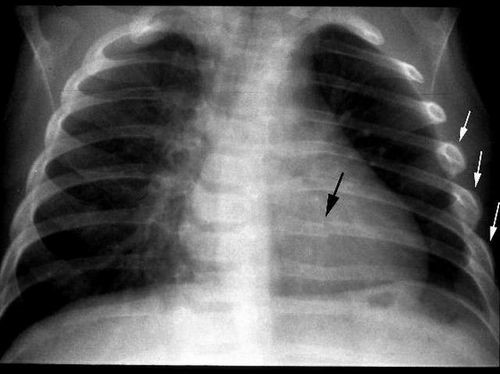

Диагноз трещина ребра врач травматолог может поставить только после медицинского осмотра. Он заключается в установке причины, определения места травмы, трещина ребра на рентгене должна быть отчетливо видна, получении послойного изображения внутренней структуры костей, наблюдении за дыханием, работой сердца и проверки общего состояния пострадавшего. Важно убедиться, что нет никаких других травм.

Во время диагностики важно определить точную травму. Часто перелом и трещина ребра имеют схожие симптомы. Перелом характерен тем, что при пальпации может слышаться хруст осколков кости, возможно смещение обломков. Важно определить точный диагноз: трещина или ушиб ребра. Точный ответ можно сказать только после проведения рентгеновского исследования. Не стоит опасаться данного назначения: вред рентгена для организма при подобном снимке ребер практически отсутствует (если, конечно, у вас нет никаких противопоказаний).

В случае, если у врача возникли подозрения на наличие осложнений, то помимо осмотра и пальпации выполняется ультразвуковое исследование органов грудной клетки и брюшной полости. Лучшим методом является рентгенография.

Главным признаком трещины ребра является «болезненность на протяжении» – при надавливании на любой участок ребра боль возникает в том месте, где произошла трещина ребра. Для подтверждения диагноза назначают: компьютерную томографию, рентгенография грудной клетки.